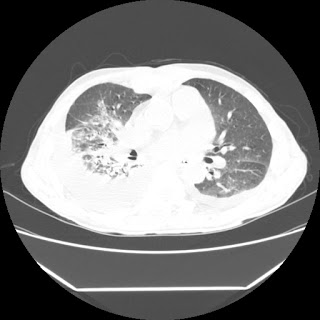

A 56 years old man with

HRCT done on summer season starting 2016